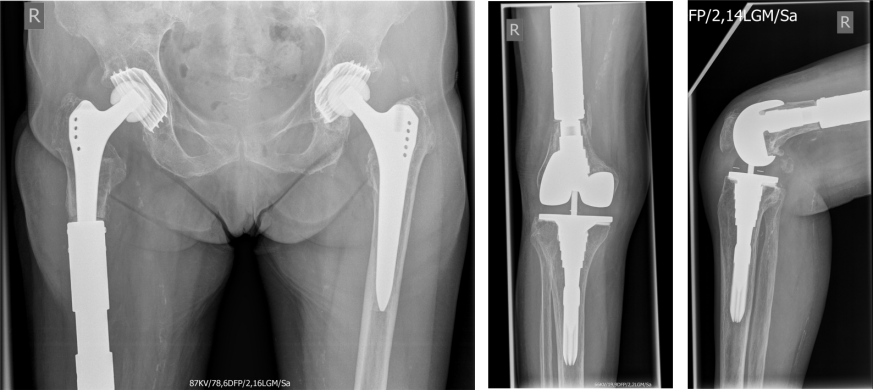

This is a report on a female patient aged 84 years at time of surgery. The patient was admitted to our center due to right-sided gonarthrosis with partial instability of the collateral ligaments and compression fracture of the medial femoral condyle (Figure 1 [Fig. 1]). In addition, she had rheumatoide polyarthritis. Therefore, we performed total knee replacement (Figure 2 [Fig. 2]) using a valgus-varus constrained LCS-Complete™ Revision System (DePuy Synthes, 325 Paramount Drive, Raynham, MA, USA).

Figure 1: Preoperative X-ray of the right knee joint

Fracture of the intercondylar fossa of the distal femur. No fracture of the tibia. No fracture of the fibula. Severe gonarthrosis. Laterally, the joint space is narrowed with pronounced subchondral marginal sclerosis and osteophytes. Subluxation position.

Figure 2: Postoperative x-ray of the right knee joint showing the correct position of the semi-constrained total knee replacement